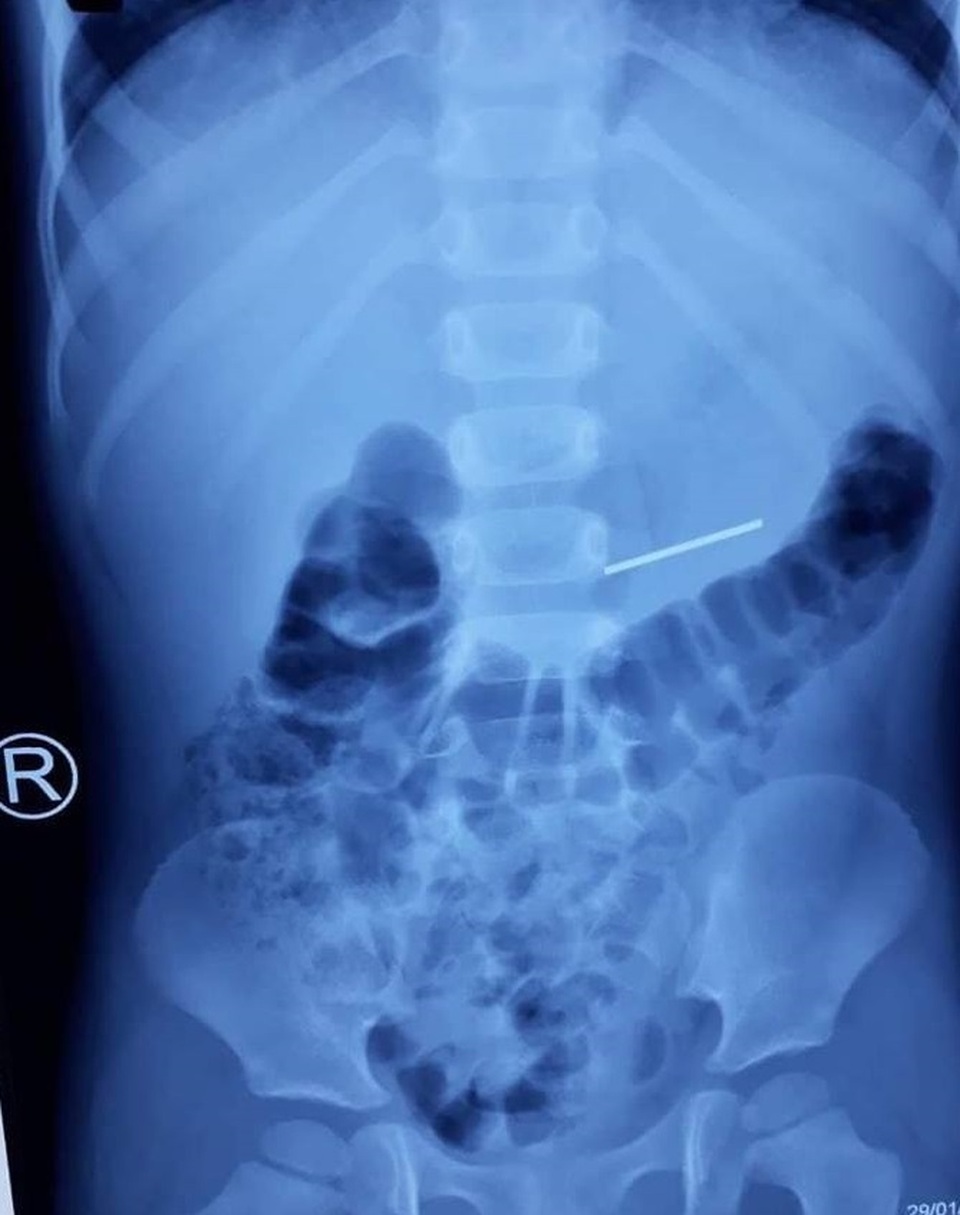

Bé trai 4 tuổi nuốt dị vật nguy hiểm

Một trương hợp khác lá bé trai 4 tuổi (ngụ tại Long An), cháu nghỉ học ở nhà, phụ huynh bận nên không để ý, trong lúc bé ngậm thanh cầu bánh xe đồ chơi, thì bị dị vật dài 3 cm, có 2 đầu nhọn trôi tuột vào dạ dày nguy cơ gây tắc, đâm thủng đường tiêu hóa. Các bác sĩ đã phải tiến hành nội soi gắp dị vật cho bệnh nhi.